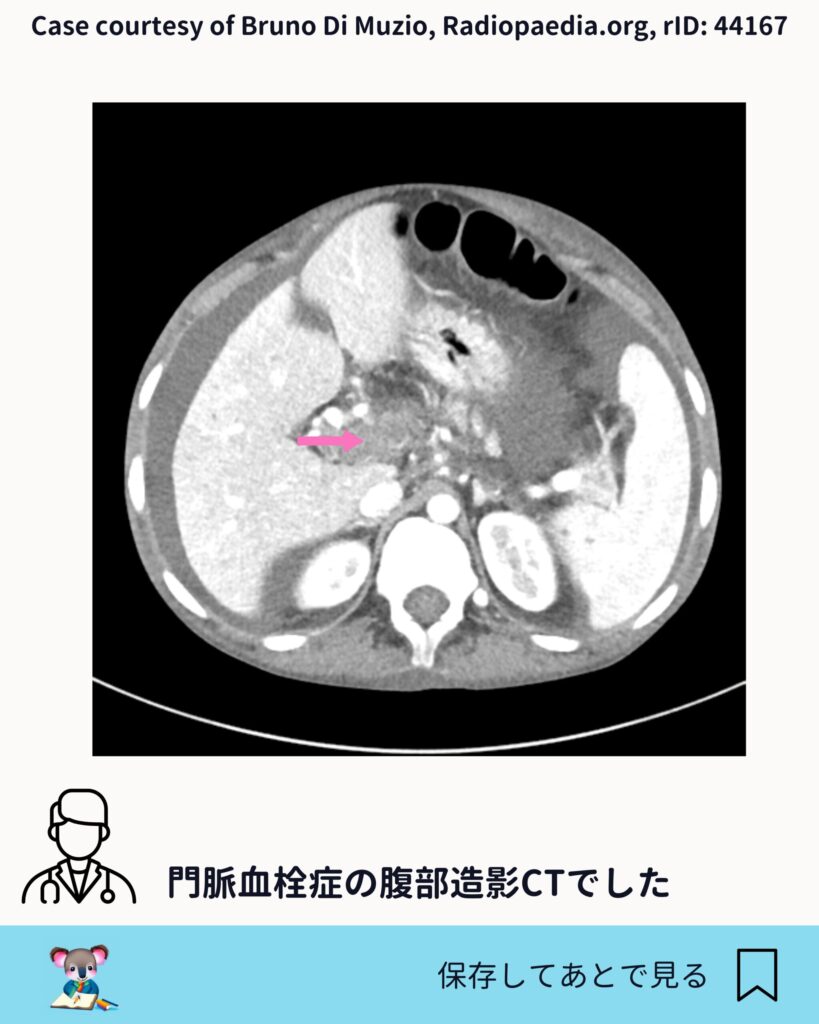

門脈血栓をどう見るか

今回の症例では、門脈内に造影欠損が認められます。スライスを追うと、はっきりとした血栓として確認できます。

門脈血栓症では、 ・門脈の拡張 ・造影欠損 ・側副血行路の有無

こうした点をセットで評価していくことが、臨床的には自然です。